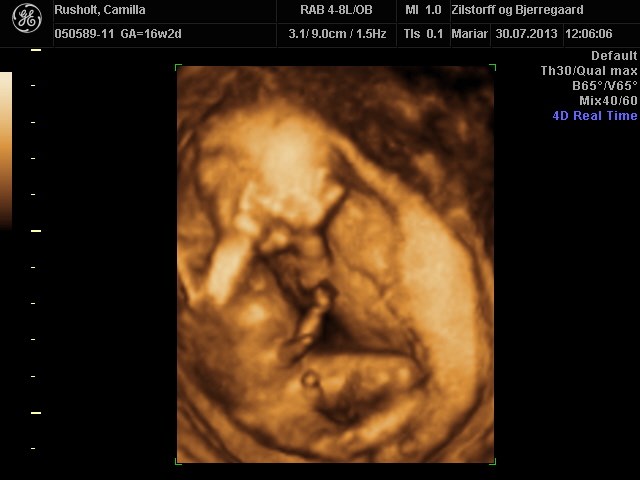

CroQuis skriver:

Årrrrrrh hvor er han fin

Hvad koster det egentlig at få 3D og alle de billeder/film med?

Vi gav 700 kr

Vi køber så også 3d/4d scanning hos dem i uge 28, og så får man så rabat på den. Den koster 1400, men vi skal kun give 1100 (fordi vi har fået kønsscanning der også), og så får vi 300 tilbage af danmark, så alt i alt 1700 kr for 3d/4d scanning samt kønsscanning med 3d